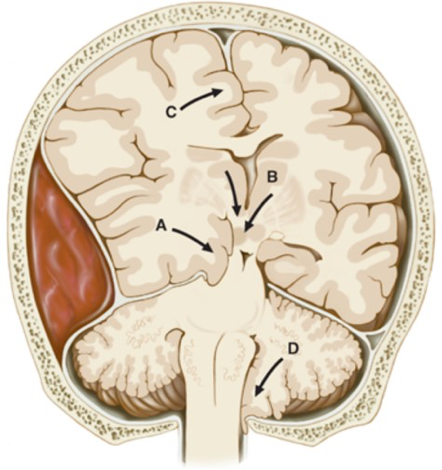

• Figure 2.3. Herniations of the Central Nervous System. Increased Intracranial Pressure and Head Trauma, Kasper DL, Fauci AS, Hauser SL, Longo DL, Jameson J, Loscalzo J. Harrison’s Manual of Medicine, 19e; 2016. Accessed July 17, 2018.

Increases in intracranial pressure leads to herniations;

A is a herniation of the temporal lobe (uncal herniation) into the midbrain or B is showing a herniation of the thalamus (central) into the midbrain can occur. Both of these herniation are the result of the tentorial notch.

A herniation of the cerebellar tonsil (foraminal) into the foramen magnum may cause death because of compression of the vital centers within the medulla (D).

A mass or swelling can force the temporal lobe inferiorly into the tentorial notch (incisura), leading to an uncal herniation. Damage to the uncus may result in disturbances in olfaction. Compression of the midbrain from an uncal herniation can lead to 3rd nerve damage that may also lead to stupor or coma if the compression is not treated. See Figure 2.3.